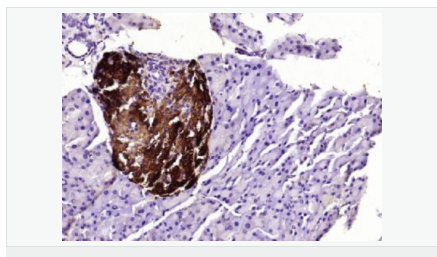

產品應用WB=1:500-2000 ELISA=1:5000-10000 IHC-P=1:100-500 IHC-F=1:100-500 ICC=1:100-500 IF=1:100-500 (石蠟切片需做抗原修復)

產品介紹This gene encodes an aldo-keto reductase that catalyzes the NADPH-dependent reduction of pteridine derivatives and is important in the biosynthesis of tetrahydrobiopterin (BH4). Mutations in this gene result in DOPA-responsive dystonia due to sepiaterin reductase deficiency. A pseudogene has been identified on chromosome 1. [provided by RefSeq, Jul 2008]

Catalyzes the final one or two reductions in tetra-hydrobiopterin biosynthesis to form 5,6,7,8-tetrahydrobiopterin.

Defects in SPR are the cause of dystonia DOPA-responsive due to sepiapterin reductase deficiency (DRDSPRD) [MIM:612716]. In the majority of cases, patients manifest progressive psychomotor retardation, dystonia and spasticity. Cognitive anomalies are also often present. The disease is due to severe dopamine and serotonin deficiencies in the central nervous system caused by a defect in BH4 synthesis. Dystonia is defined by the presence of sustained involuntary muscle contractions, often leading to abnormal postures.